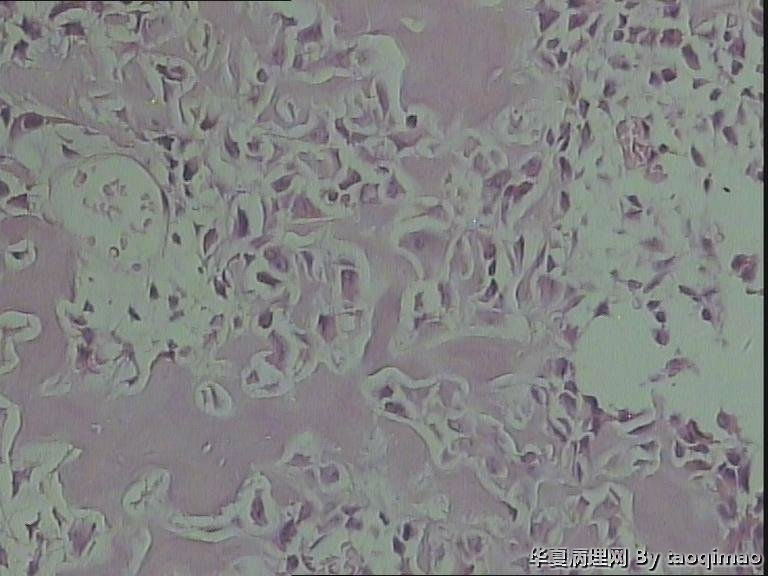

• 肋骨肿物,求助图4

图4

患者女,31岁,胸部CT第八肋骨肿瘤,肿物在肋骨内突出骨外膜,大小2.3X1.5.切面灰白质韧

这是一部分容易取下来的肿瘤,其余部分还在脱钙中

骨母细胞瘤。矿化不均要除外骨母细胞型骨肉瘤,虽然肿块小了点。还是找找核分裂,看看X线的好。

那就是骨样骨瘤。